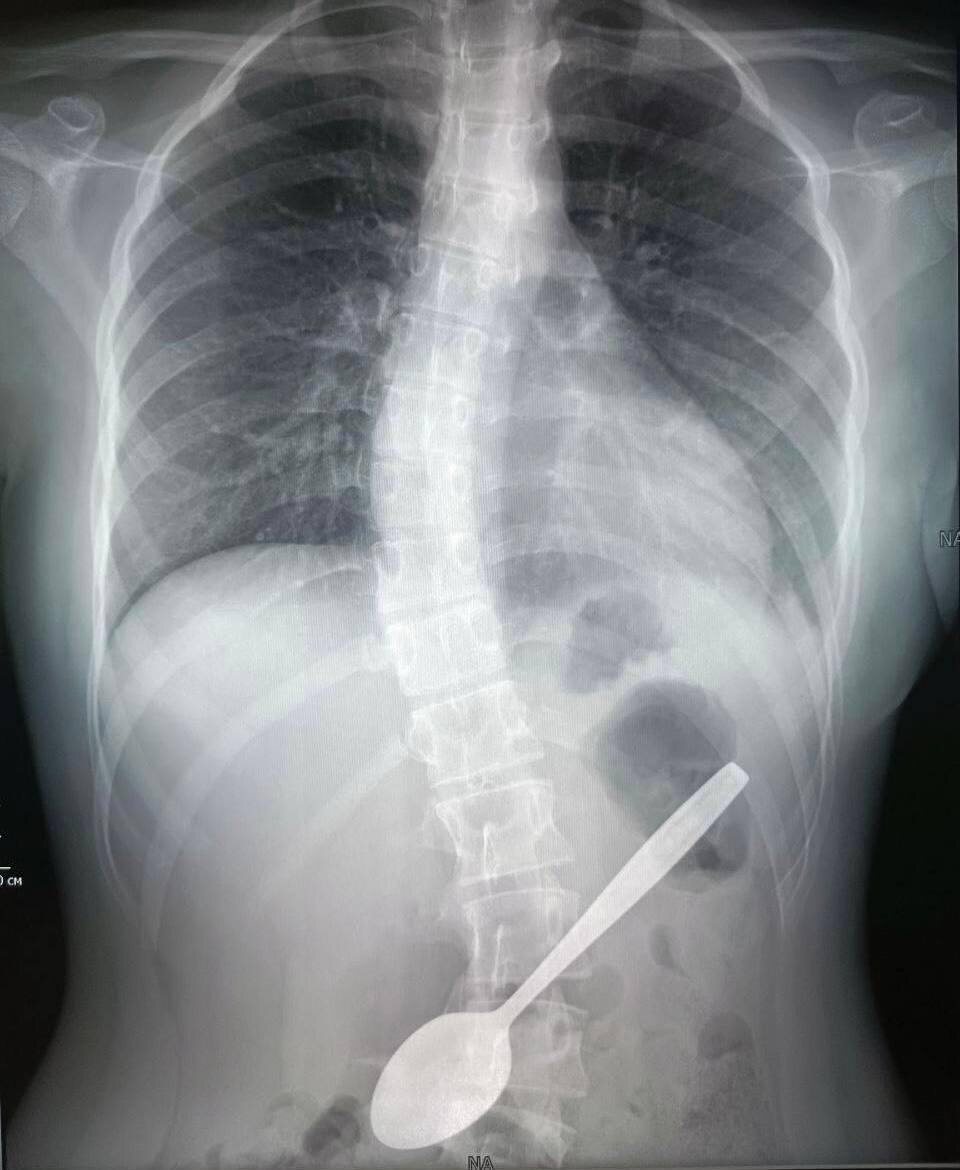

Хотела достать кусок яблока из горла, а проглотила ложку: врачи вытащили столовый прибор из желудка 14-летней девочки

Подросток решила с помощью 15-сантиметровой чайной ложки достать застрявший в горле кусок фрукта. Однако что-то пошло не так, и девочку пришлось везти в подмосковную больницу. Там школьнице за час вытащили инородный предмет из желудка. Пострадавшую выписали и отправили домой.